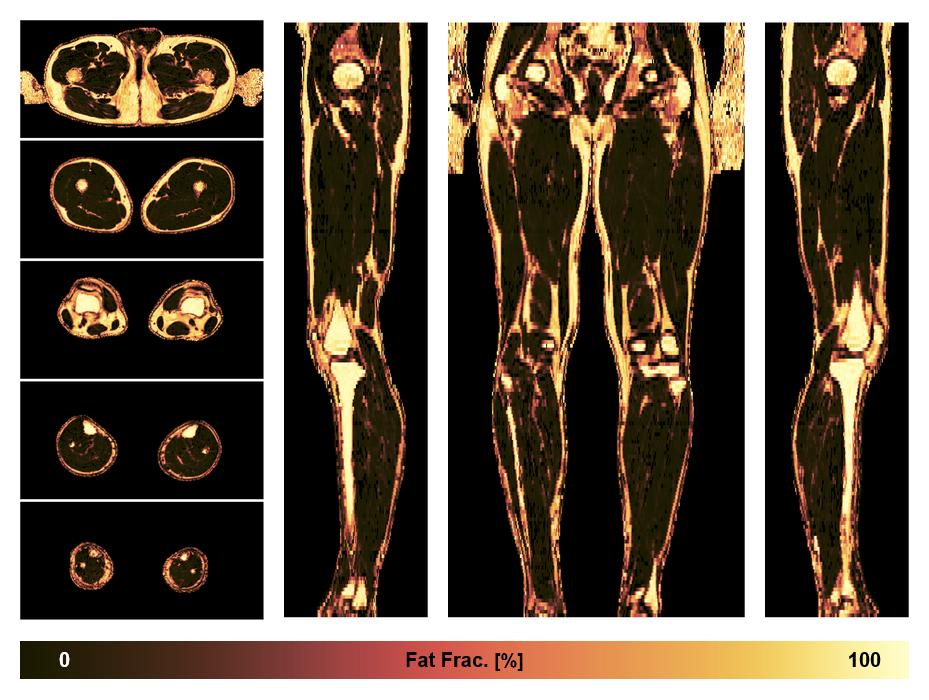

• Fat fraction

The fat fraction of the lower extremity obtained from the dixon reconstruction for muscle water fat quantification.